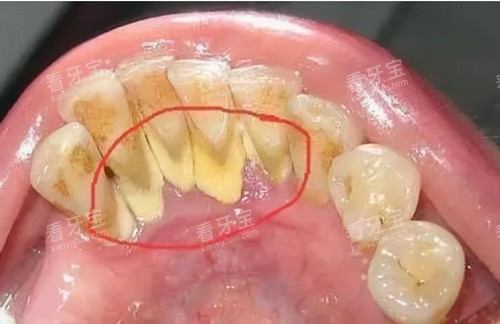

下前牙内侧:牙结石的“老巢”

舌头舔到下牙内侧有粗糙感?赶紧打开手机手电筒,45度角斜照牙面。要是看到米粒大小的乳白色凸起,或者黄褐色硬块卡在牙龈边缘——恭喜你,中招了!这个位置唾液腺发达,细菌更爱在这儿“安营扎寨”。